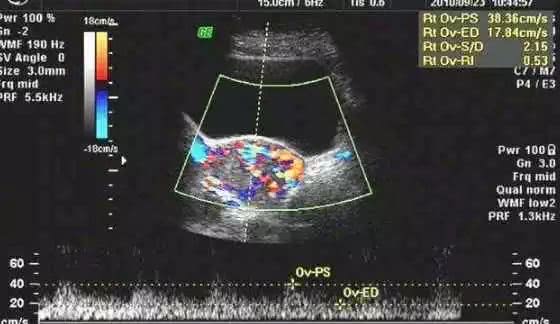

葡萄胎是指胎盘绒毛发生水肿,形成大小不等的一串串水泡,水泡串联在一起,形似葡萄,故称“葡萄胎”,一般而言,葡萄胎组织上还可见胚胎或胎儿,但是通常都已死亡。

(葡萄胎)